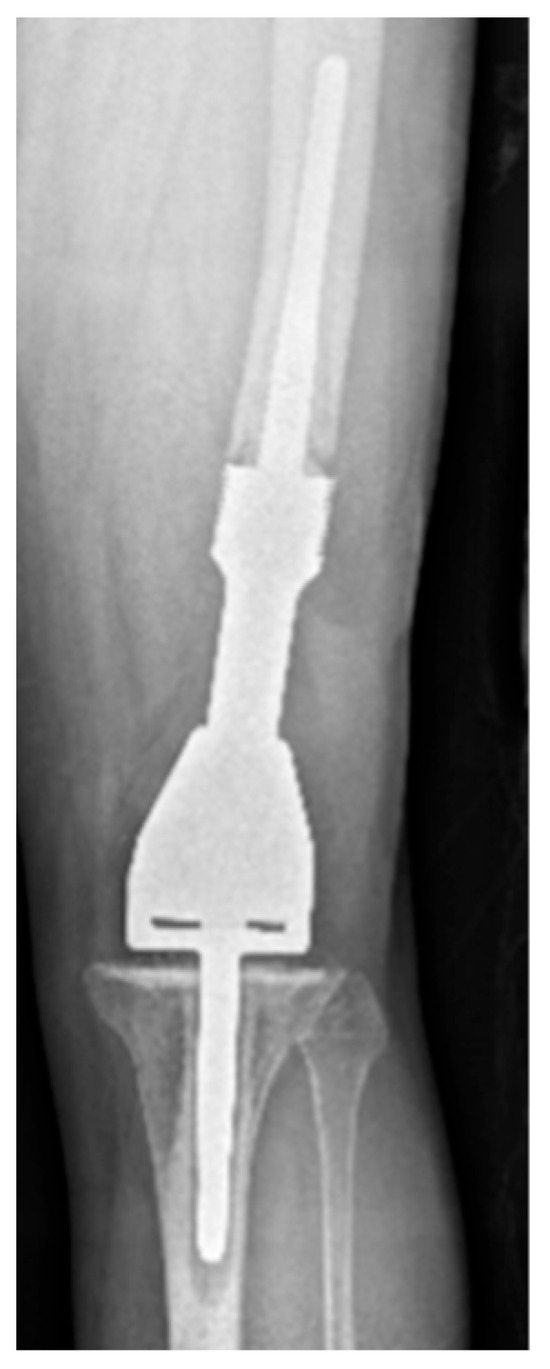

| Grade of loosening | |

| Grade 2 | 5 (17.9) |

| Grade 3 | 16 (57.1) |

| Grade 4 | 2 (7.1) |

| Grade 5 | 1 (3.6) |

| Grade 6 | 4 (14.3) |